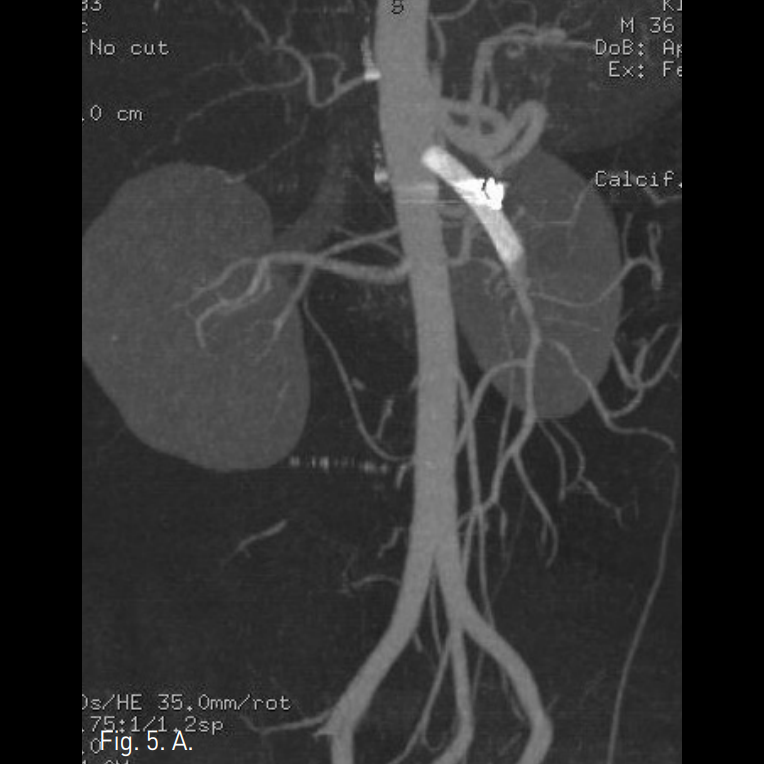

시술 후 시행한 상장간막동맥조영술상 dissecting aneurysm은 폐색되었고 상장간막동맥의 flow는 잘 유지되었다(Fig. 6). 시술 1주 후 시행한 CTA상 상장간막동맥의 벽내혈종은 그 양이 감소하였고, luminal narrowing은 호전되었으며, 동반된 합병증은 없었다(Fig. 7A, B).

Fig. 7

A, B. Oblique sagittal reconstructed MIP image (A) and volume rendered 3D CTA (B) obtained 1 week after procedure reveal patent SMA with decreased intramural hematoma and no residual filling of contrast media at the embolized aneurysm.